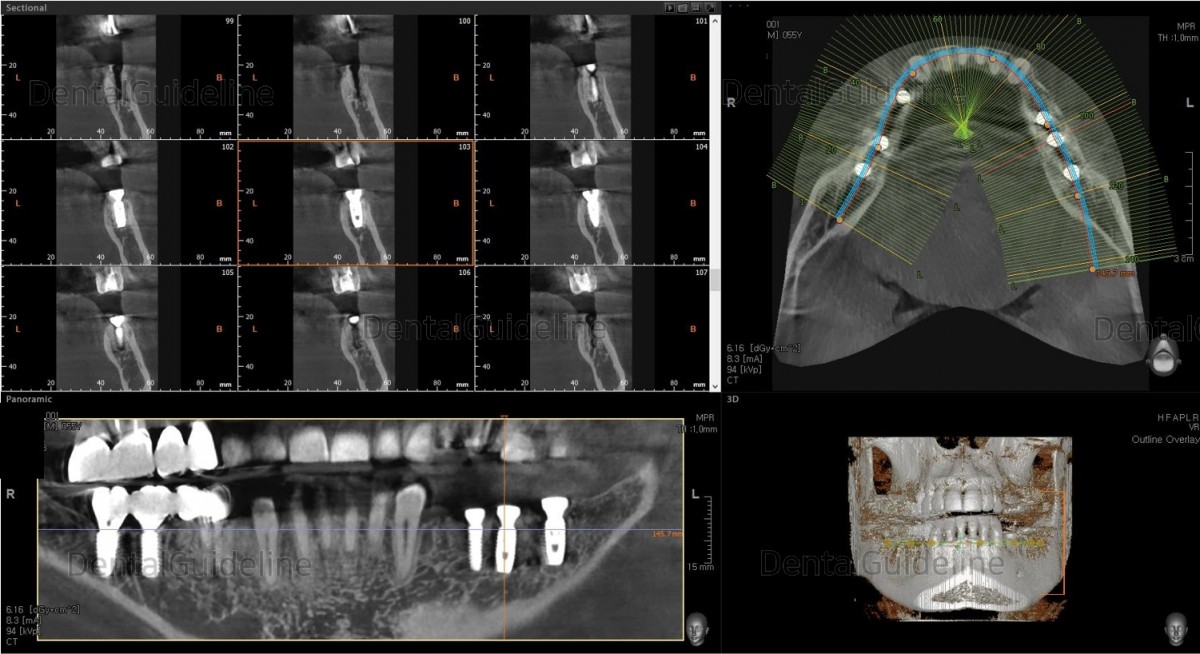

Surgery simulation to find the optimal

size, position, and direction of implants.

2nd premolar –Arum NB

Ø4.0L10 (30Ncm), 1st molar-Arum NB

Ø5.0L10 (40Ncm), 2nd molar-Arum NB

Ø5.0L10 (30Ncm),

The panoramic radiograph.